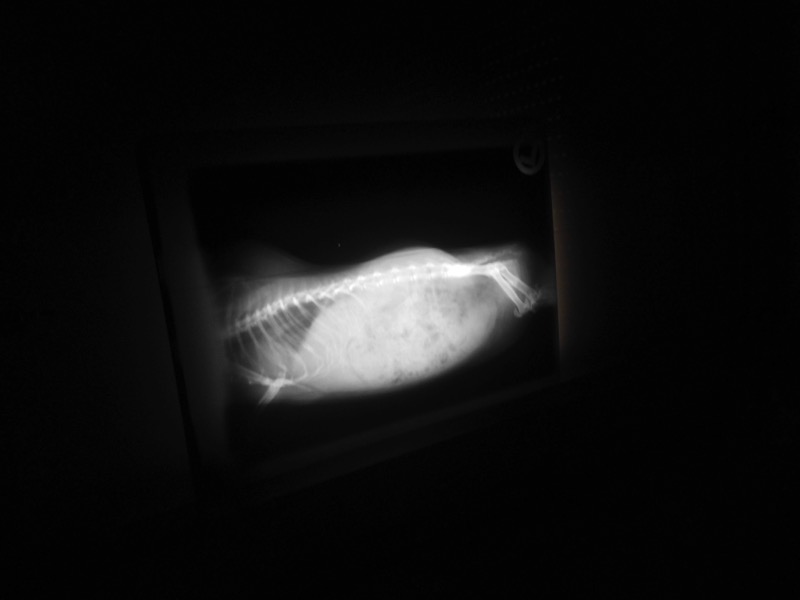

Unsere Tiere waren alle ohne Befund. Ein Meerschweinchen musste zur genauen Abklärung noch geröntgt werden. So sind wir nun erst einmal wieder beruhigt.